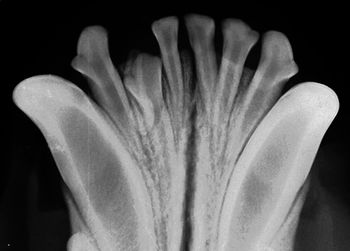

Missing or extra teeth must be caught early to prevent more serious dental problems down the line.